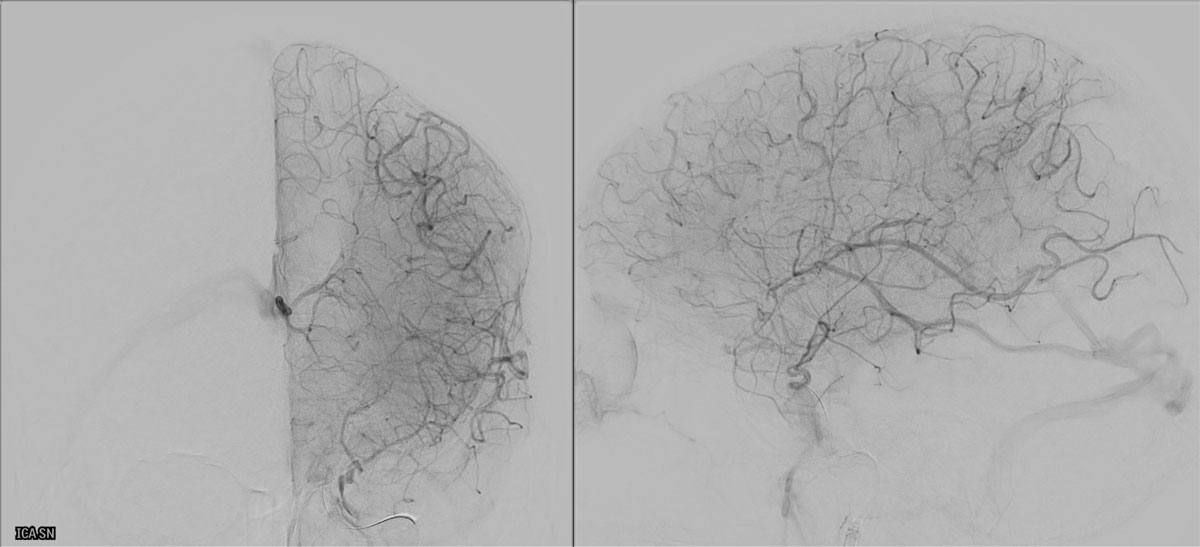

EVT Strategy

• Inflate the balloon, in order to dilate the true lumen

• MCA access with the softest system possible

• Open a stentriever for 20 mins with antiplatelet infusion

• Resheath the stentriever, check patency, if not stent-deployment

Headway™ DUO 156cm / Traxcess™ 14

CatchViewMini20

pEGASUS 4x20mm